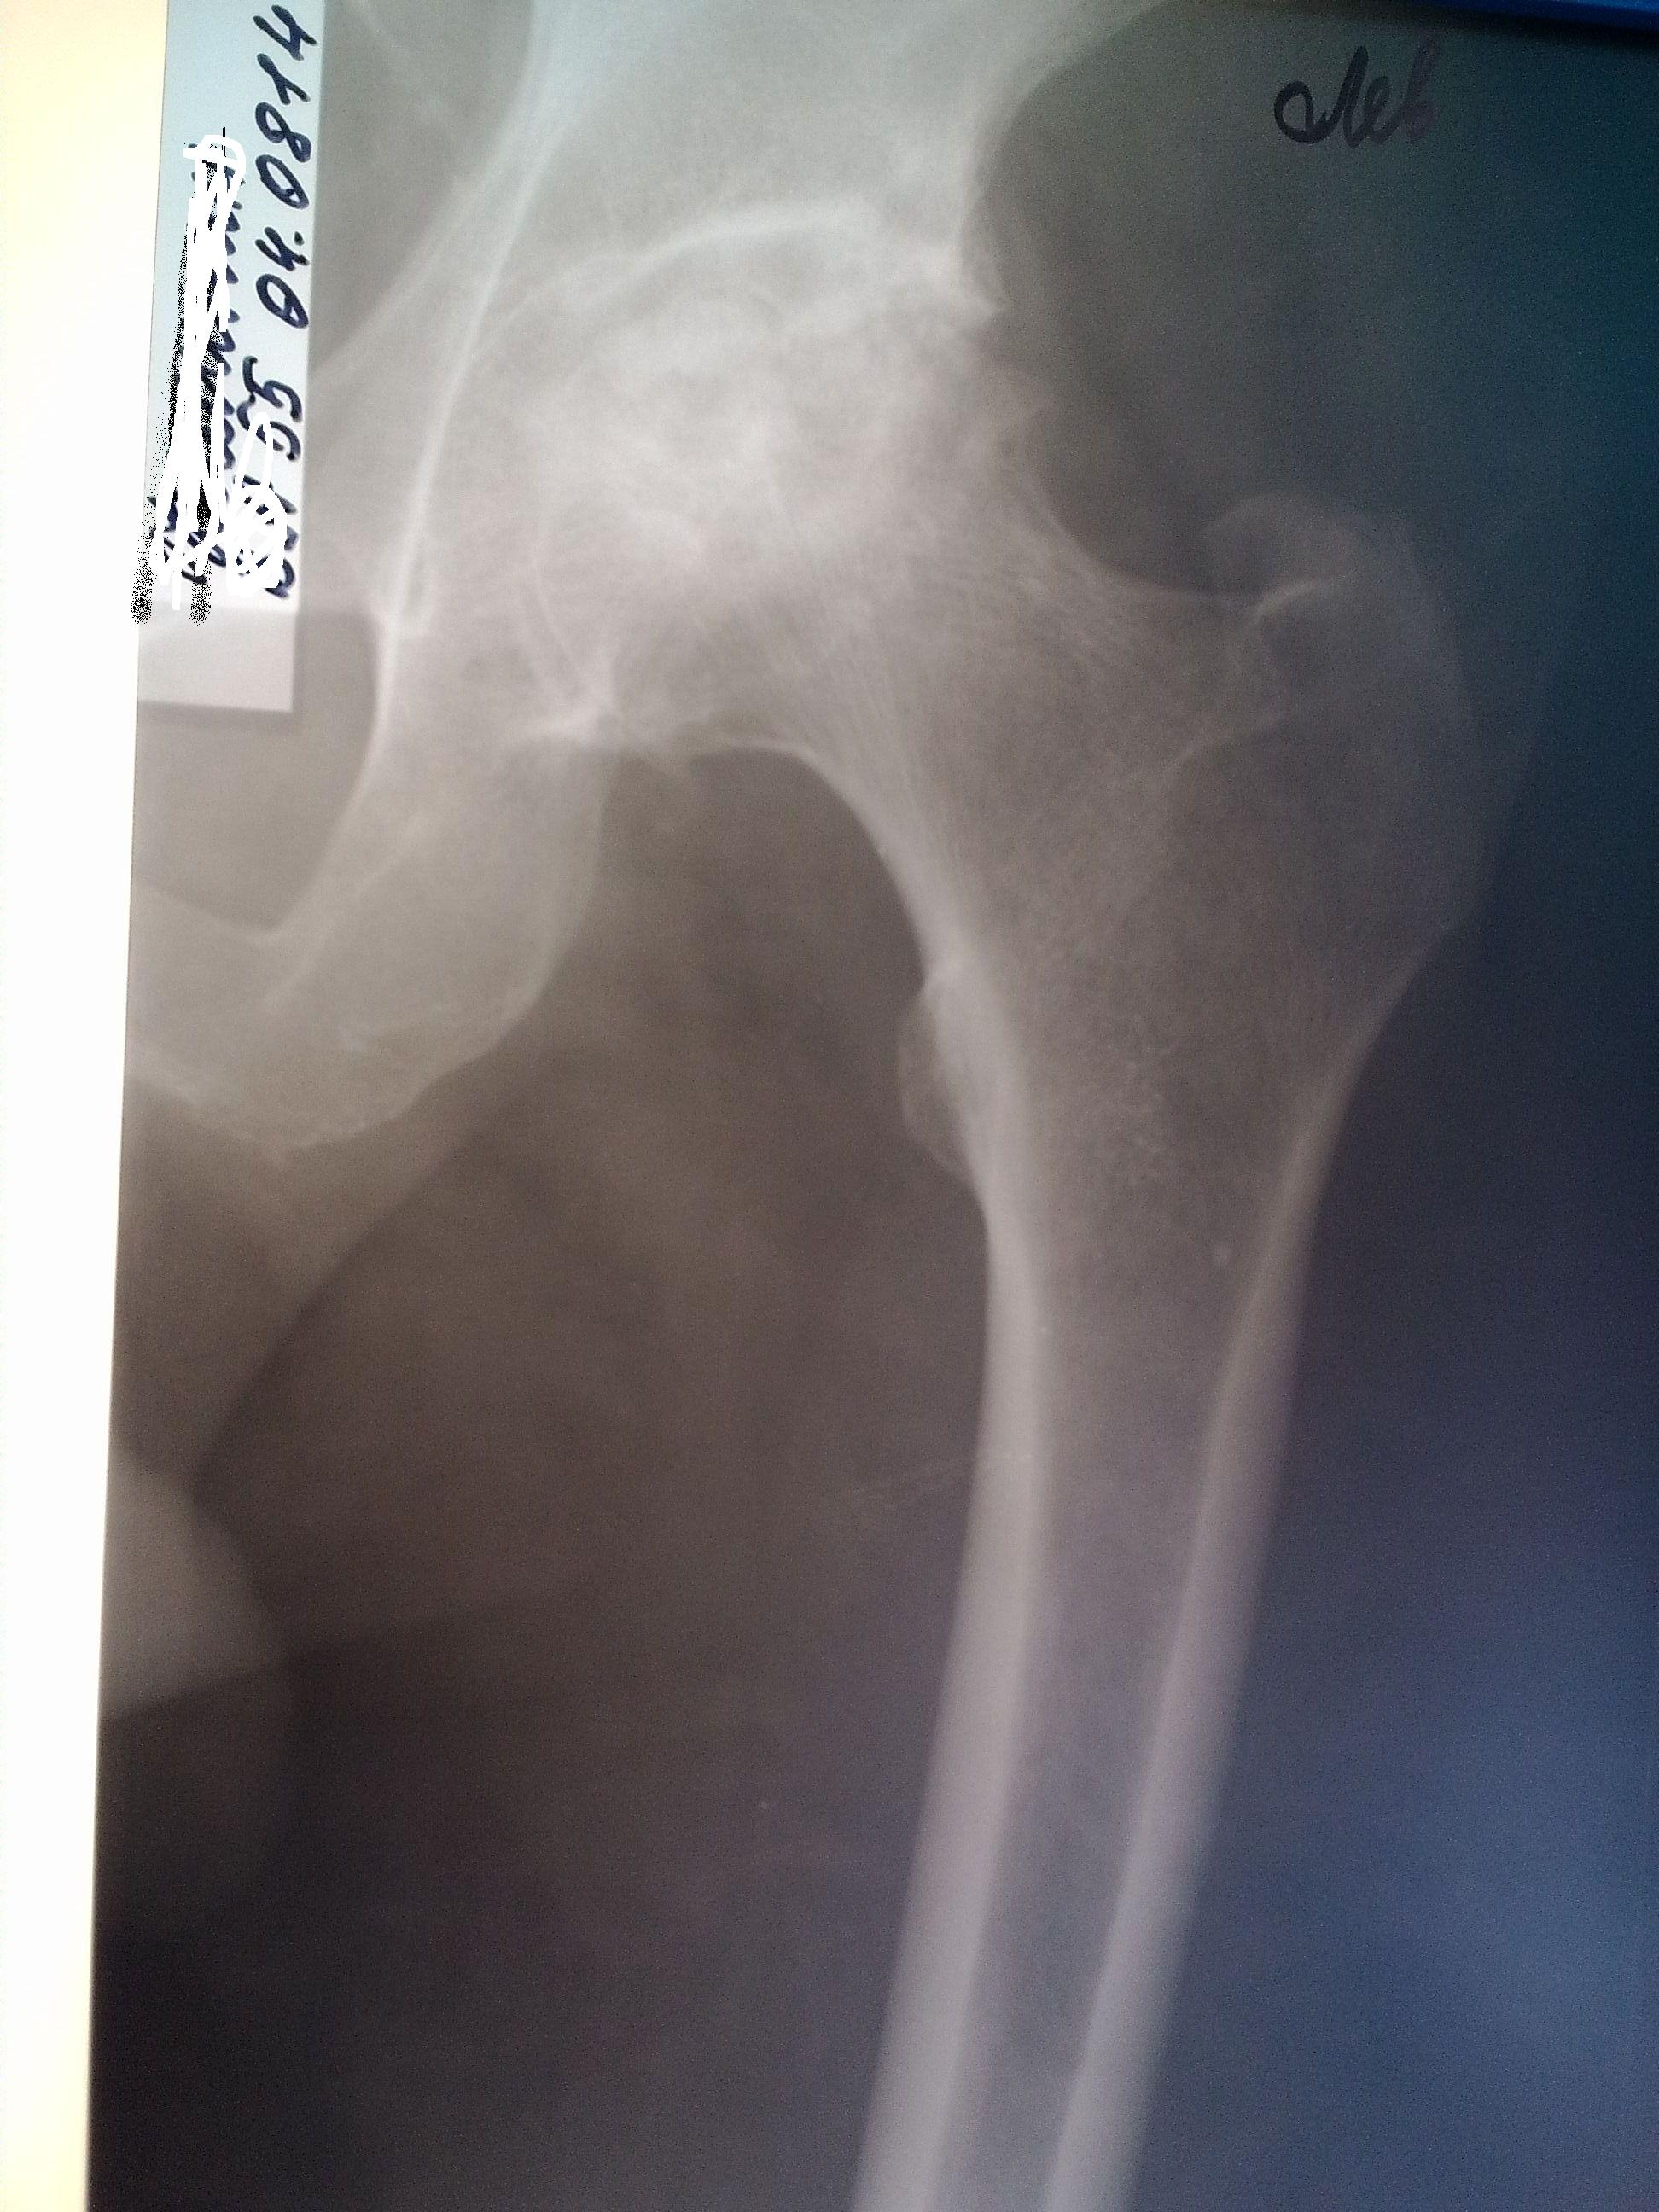

Диагностика ТБС рентгеном и асептический некроз: особенности лечения

Раздел: Снимки-откровения